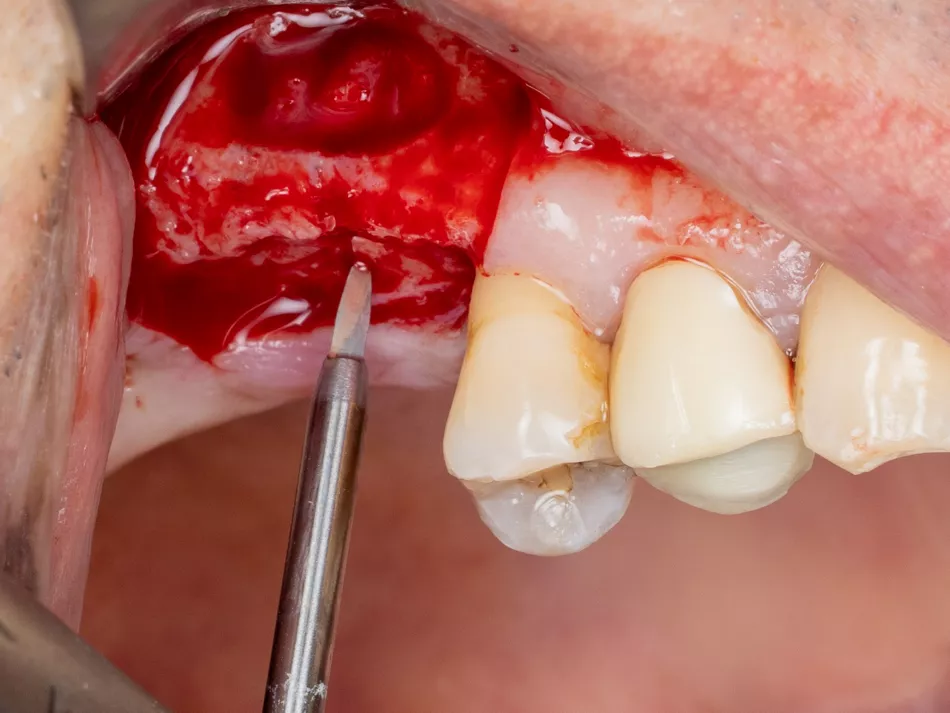

6. Placement of a saline-impregnated collagen sponge to assist the detachment by conferring increased but gentle and evenly distributed pressure.

7. Sinus mucosa detached.

8. Verification of the absence of mucosal adherence at the Beta angle and at the inter-sinus-nasal septum using a Freer sinus elevator.